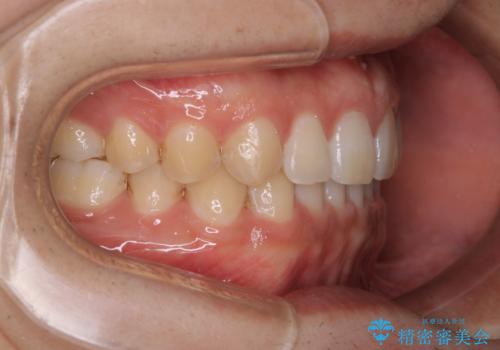

- 上のすきっ歯が気になるとご相談にいらした方です。上下顎ともにスペースがあったため、インビザラインFULLにて見た目と噛み合わせの改善も同時に行いました。

元々は上前歯のみの部分矯正をご希望されていましたが、下の歯もスペースがあり、噛み合わせ的にも上のみの部分治療は難しいことをお話ししました。前歯のみの部分矯正を行った場合、前歯の隙間だけが閉じて奥歯が噛めなくなってしまう場合もあります。インビザラインFULLにて治療することで、噛み合わせと見た目を同時に改善させることができ、大変喜んでいただけました。